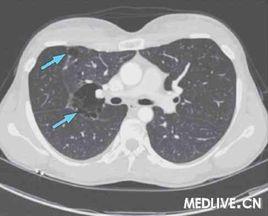

繼發自發性氣胸多原有肺過度膨脹,叩診呈過清音,觸診震顫及肺呼吸音均明顯減低,當氣胸發生時,體格檢查雙側往往無明顯差別。確立繼發自發性氣胸的診斷是胸部X線片。但慢性阻塞性肺疾患發生氣胸時,X線片可表現為局限性氣胸或病肺萎陷不完全。有時還需要與大的肺大泡相鑑別。CT掃描檢查,有助於判別肺內的原發性病灶。